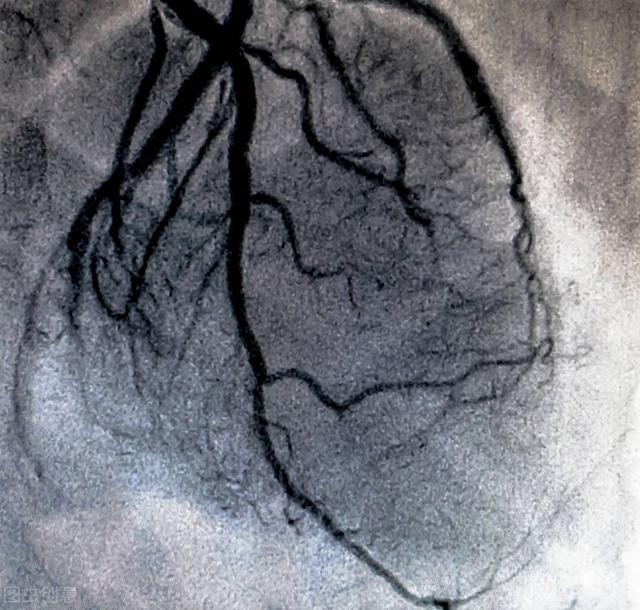

(1) Qu'est-ce que la maladie coronarienne ?Il arrive souvent que des patients disent ressentir une gêne dans la poitrine ou que le rapport de l'ECG suggère des modifications du segment st et demandent s'il s'agit d'une maladie coronarienne. La maladie coronarienne est due à l'athérosclérose des artères coronaires, la plaque d'athérome s'agrandit progressivement, la lumière se rétrécit progressivement, lorsque le rétrécissement de la lumière est supérieur à 50 %, l'activité peut apparaître dans le cœur, l'apport sanguin est insuffisant, ce qui entraîne l'apparition des symptômes de l'angine de poitrine, l'électrocardiogramme peut se manifester par une modification du segment st.Un diagnostic préliminaire de la maladie coronarienne peut être établi en analysant les symptômes cliniques typiques du patient, ainsi que son sexe et son âge, et les facteurs de risque, tels que l'hypertension artérielle, l'hypercholestérolémie, le tabagisme, le diabète, l'obésité, etc. Mais il est impossible pour un médecin de vous dire quelle artère coronaire est bouchée et à quel pourcentage, si elle est bouchée à 50 % ou à 90 %. Si vous devez déterminer l'étendue de l'obstruction ou résoudre une sténose sévère, vous devrez subir une angiographie coronarienne.

(2) Diagnostic de la maladie coronarienne :Pour les médecins cardiovasculaires expérimentés, le diagnostic de la maladie coronarienne par les méthodes ci-dessus est neuf fois sur dix exact. La coronarographie est l'examen de référence pour le diagnostic de la maladie coronarienne, car elle permet de voir clairement l'obstruction de l'artère coronaire. Bien entendu, pour certains patients, l'angiographie coronarienne peut également être utilisée comme alternative.

(2) Étapes spécifiques : le patient est allongé sur le lit d'opération dans le laboratoire de cathétérisme cardiaque, le site de l'opération est désinfecté (main ou cuisse), un anesthésique local est administré dans cette zone, un trou est pratiqué dans le vaisseau sanguin artériel à l'aide d'une aiguille, un fil-guide fin et un cathéter sont envoyés, et le cathéter à fil-guide peut atteindre les artères coronaires en suivant les vaisseaux sanguins sous le contrôle de la radiographie, puis un type de médicament (agent de contraste) est injecté dans la tête du cathéter fin, ce qui fera apparaître les vaisseaux sanguins sous les rayons X, et la taille, le trajet, l'obstruction n'est pas visible, les artères coronaires gauche et droite, chaque branche, etc. d'un seul coup d'œil. Les vaisseaux sanguins apparaissent sous la radiographie et l'on peut voir d'un seul coup d'œil leur taille, leur trajet, s'ils sont obstrués ou non, ainsi que les artères coronaires gauche et droite et les différentes branches des artères. Si le problème n'est pas grave, c'est la fin, on retire le cathéter, on ponctionne le poignet à l'aide d'un compresseur pour éviter les saignements. L'ensemble du processus prend 10 à 30 minutes si vous êtes compétent. Si le problème est grave, le traitement (dilatation par ballonnet, pose d'un stent, etc.) peut se poursuivre et prendre plus de temps.